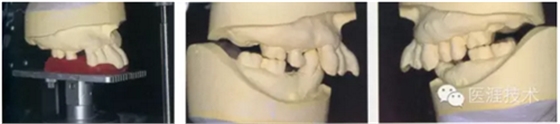

02,初診取模(取研究模型)

03,使用咬合平面分析器獲取正中矢狀面為基準(zhǔn)的咬合平面并向頜架轉(zhuǎn)移 上頜模型上頜架,下頜模型根據(jù)上頜模型位置,臨時(shí)上頜架。

04,為了使用弓描將咬合抬起高,使用哥特式弓描測(cè)量髁導(dǎo),根據(jù)根據(jù)髁導(dǎo)測(cè)量設(shè)定髁導(dǎo)斜度